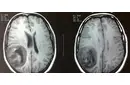

4. Potansiyel Komplikasyonlar Ameliyat sonrası komplikasyonlar, hastanın genel sağlığını etkileyebilir. Bunlar arasında:

Komplikasyonlarla Başa Çıkma

Beyin ödemi gibi komplikasyonlarla karşılaşanlar için, bu durumu aşmak için çeşitli yöntemler bulunuyor. Fiziksel terapi, doktor önerileri doğrultusunda düzenli olarak yapılmalı ve gerektiğinde psikolojik destek de alınmalıdır. Bu tür durumlar, destek gruplarına katılarak veya benzer deneyimleri yaşamış insanlarla iletişim kurarak daha kolay aşılabilir. Bu süreçte, kendinize karşı nazik olmalı ve iyileşme sürecine zaman tanımalısınız.